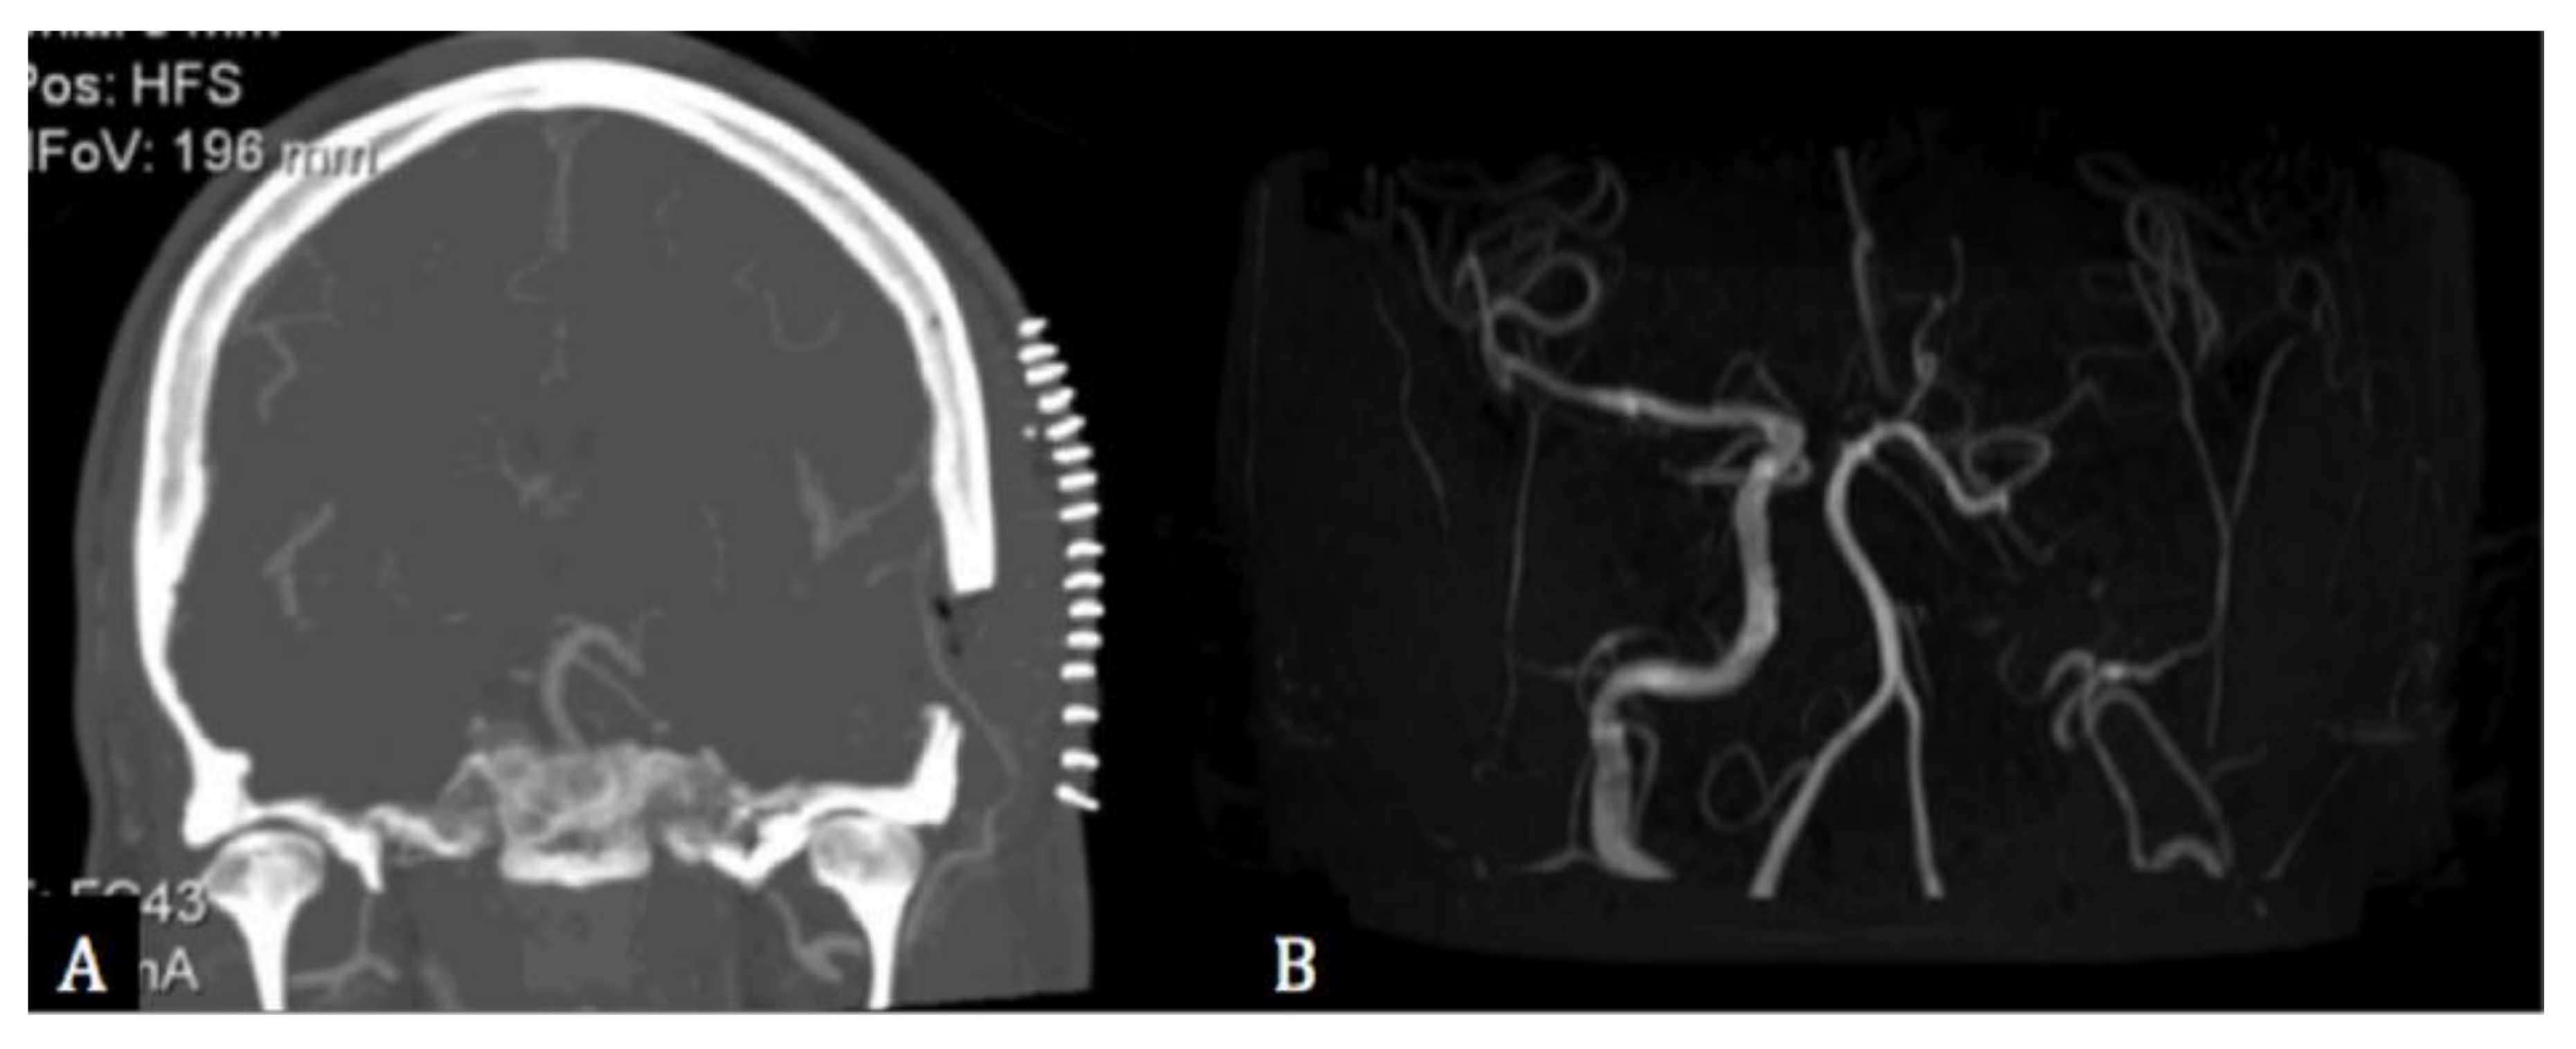

2. Case Description